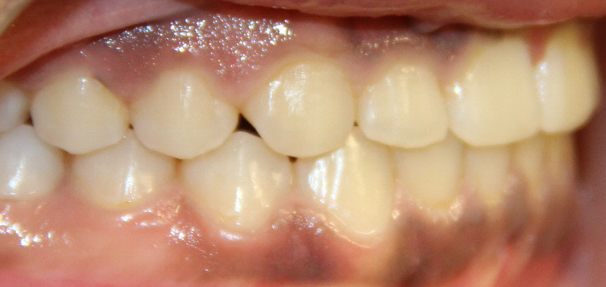

Crossbite

A crossbite occurs when one or more of the upper teeth bite on the inside of the lower teeth. It can occur in the front of the mouth or on the sides, where its usually a bilateral condition. Early correction of a crossbite is recommended because it can lead to permanent problems including asymmetric jaw growth, irregular muscle function and altered tooth eruption.

Crossbite should be corrected because it can:

- cause premature wear of the teeth

- cause gum disease including bone loss

- cause asymmetrical development of the jaws

- cause dysfunctional chewing patterns

- make your smile less attractive

How can a crossbite be orthodontically corrected?

If there is a single tooth in crossbite, the tooth can be moved into the correct position with braces. When multiple teeth are in crossbite, the arch needs to be expanded with braces or a combination of braces and an intra-oral appliance. This will help correct the bite relationship and allow the jaws to grow in harmony.

Before and After photos: Crossbite Treatment